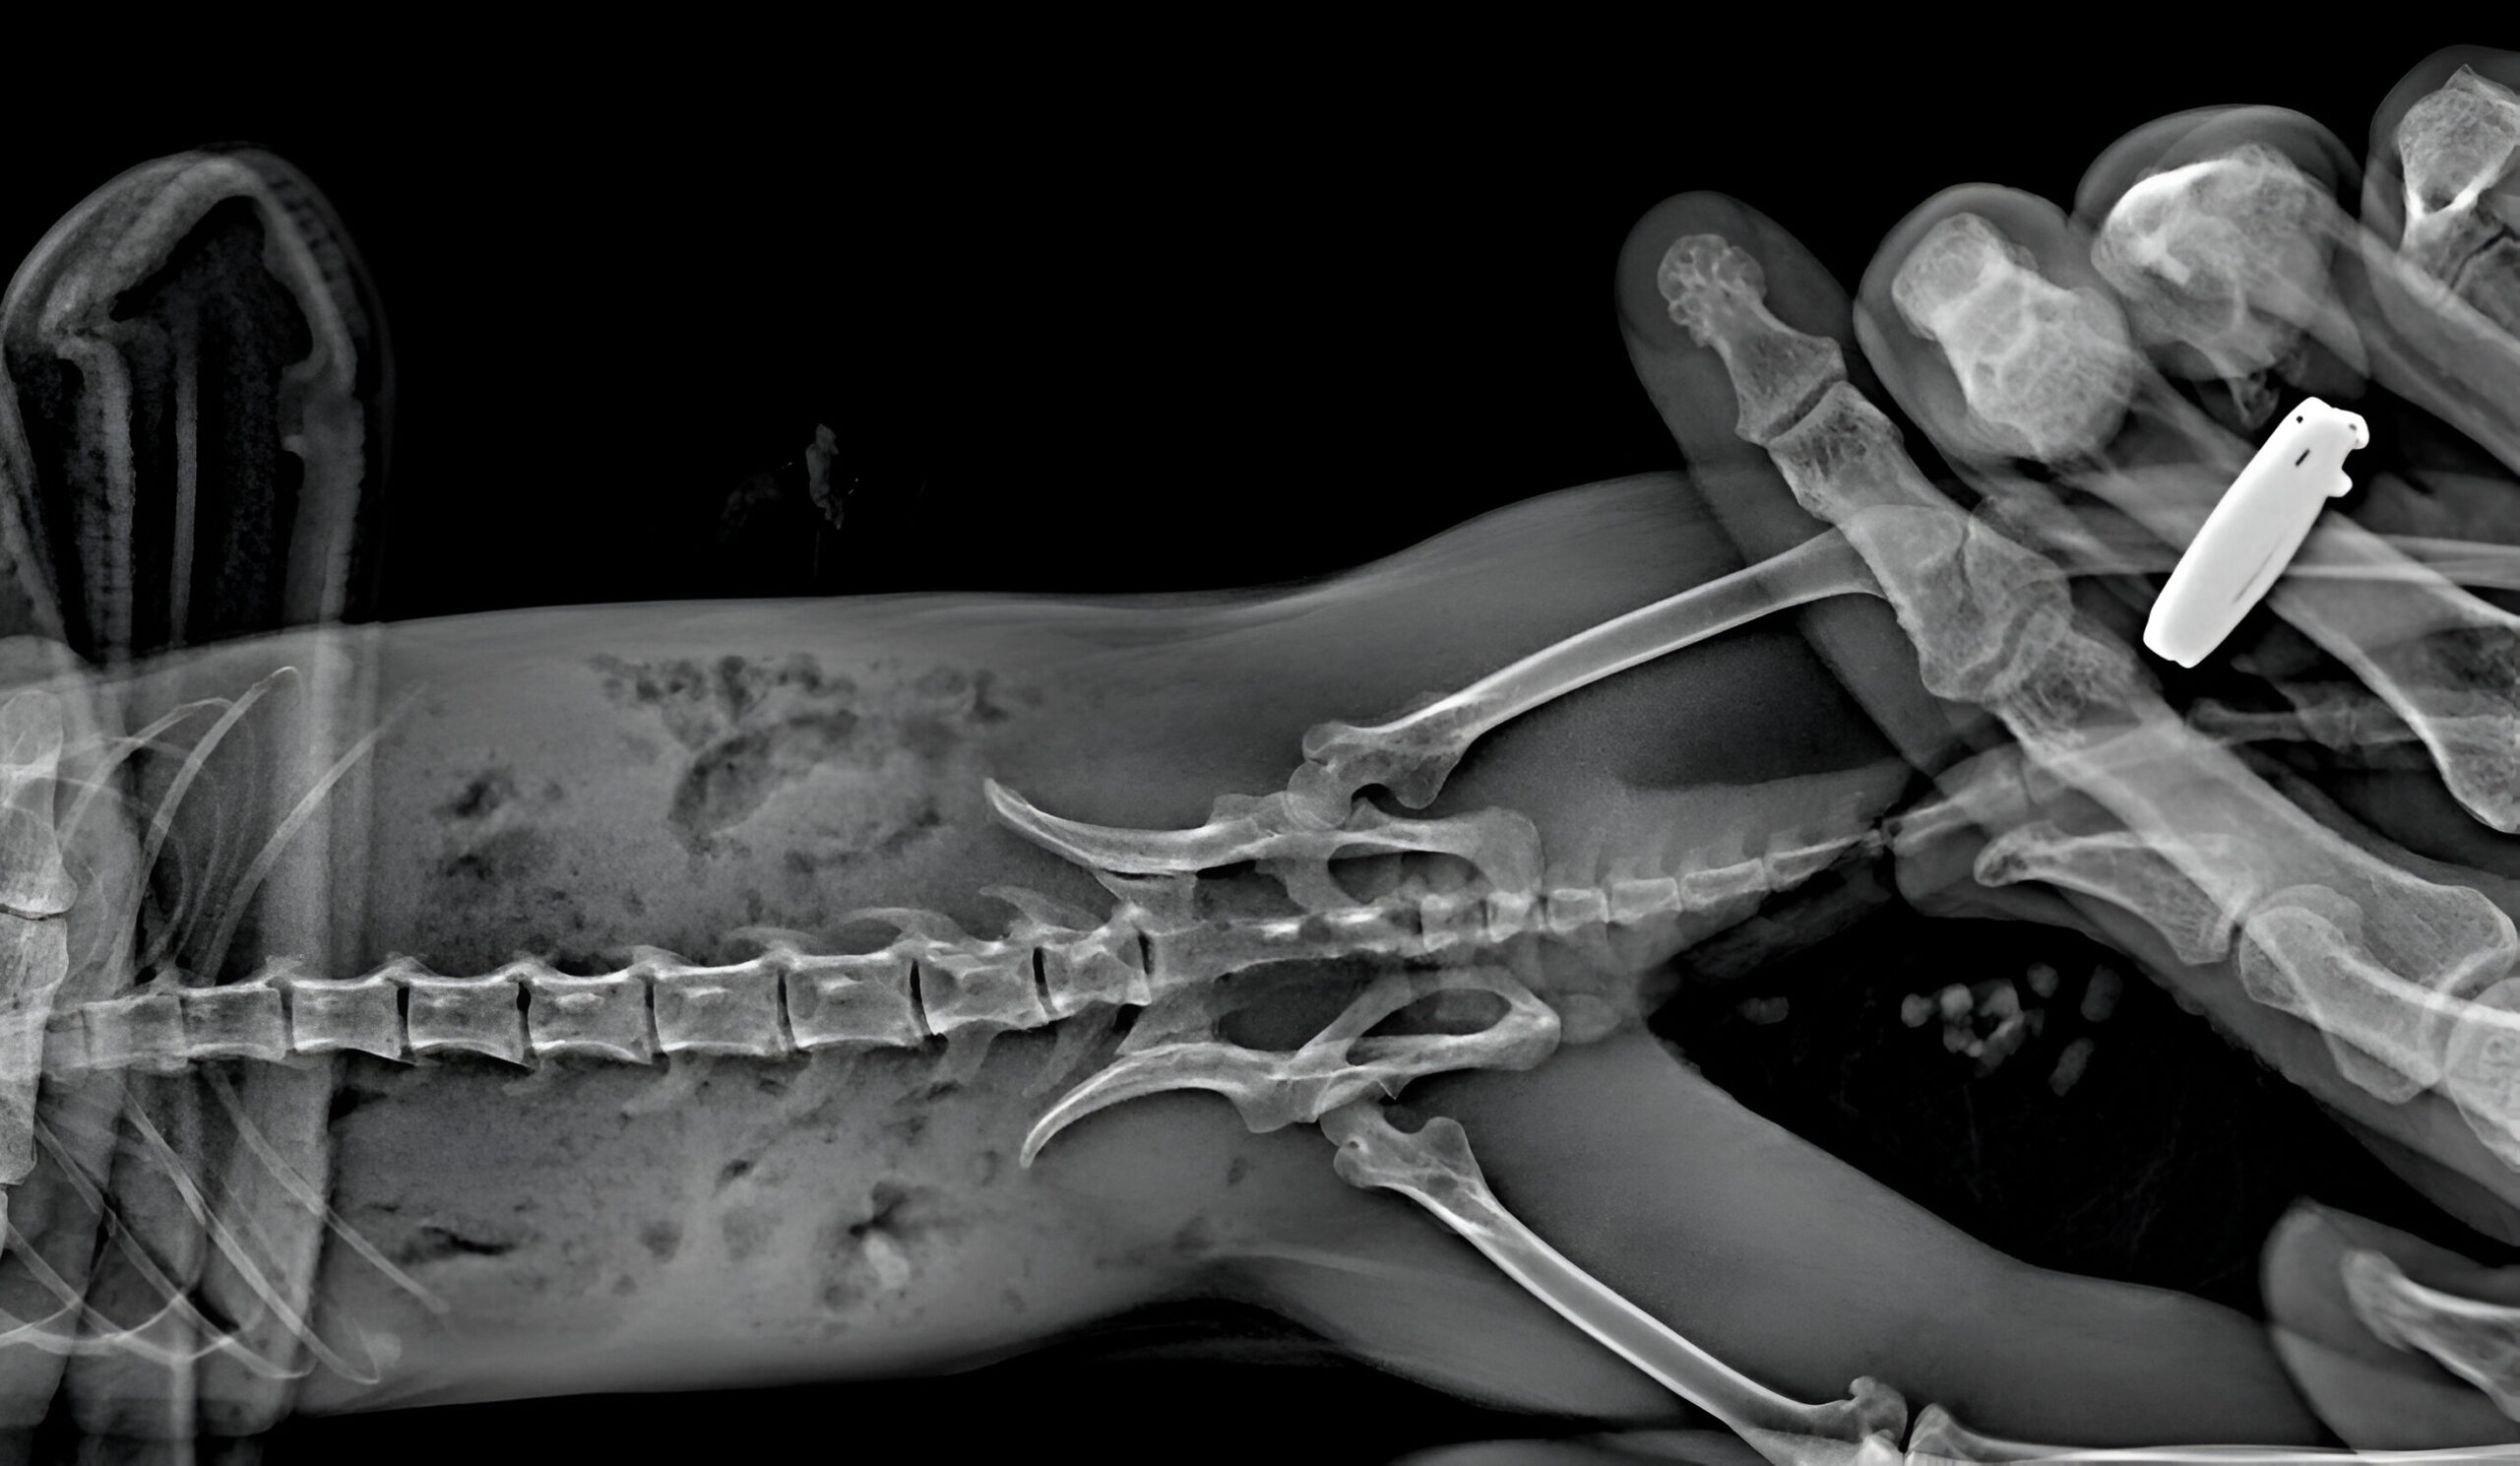

На рентгене выяснили, что у Миланы компрессионный перелом позвоночника — для белки смертельный из-за пережима спинного мозга и отказа задних конечностей. Доктор Васин сказал, что если Милана не сможет сама ходить в туалет — скорее всего, погибнет.

Рентген белки Миланы. Фото: «Белкоспас»

Милана оказалась сильной и уже через несколько дней сама начала ходить в туалет, а после 10-дневного лечения сама начала разрабатывать лапы, и одна из них снова заработала. В природу она не вернется, поэтому мы пристроили ее в хорошие руки. Недавно Милана ездила со своей новой семьей в Краснодар, и волонтер передал нам, что и вторая лапа начала восстанавливаться. Вот такое желание жить у белки.